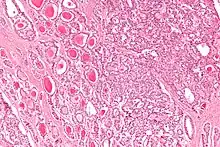

| Micrograph of a strumal carcinoid. H&E stain. |

The strumal carcinoid is a type of monodermal teratoma with histomorphologic features of (1) the thyroid gland and (2) a neuroendocrine tumour (carcinoid).[1][2]